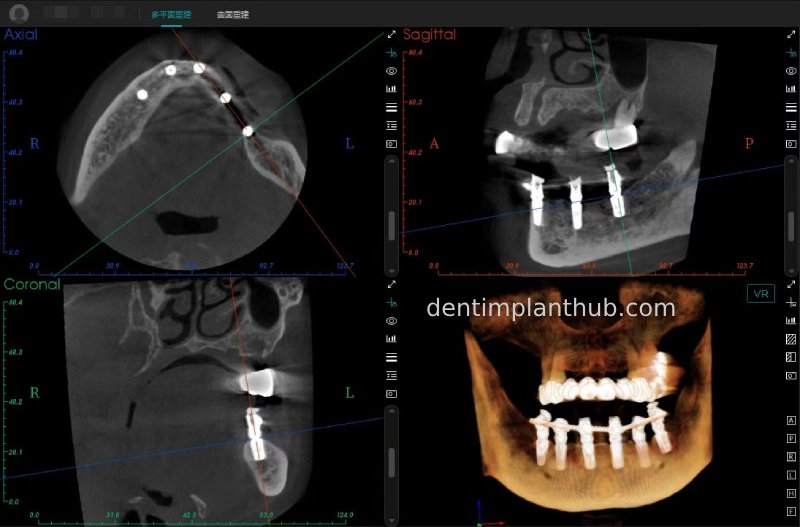

Post-surgical CBCT review photos

16

14

12

22

24

26